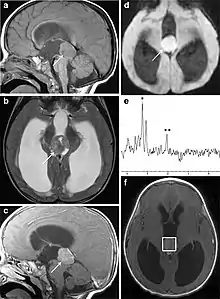

Pineoblastoma on brain imaging

Histology of pineoblastoma

Several imaging methods can be used to diagnose pineoblastoma. Initially, urgent CTs are recommended, followed by MR imaging.[13] CT will show large, multilobulated masses with heterogenous contrast enhancement and peripheral calcification of the pineal gland.[4][3] On MRI, pineoblastomas again appear as masses with heterogenous enhancement. They often appear hypo- to isointense on T1 and slightly hyperintense on T2-weighted images. Some areas of necrosis or hemorrhage may be seen as well. PET-CT has also been used in diagnosis, and shows increased uptake of fludeoxyglucose with pineoblastomas compared to other pineal masses.